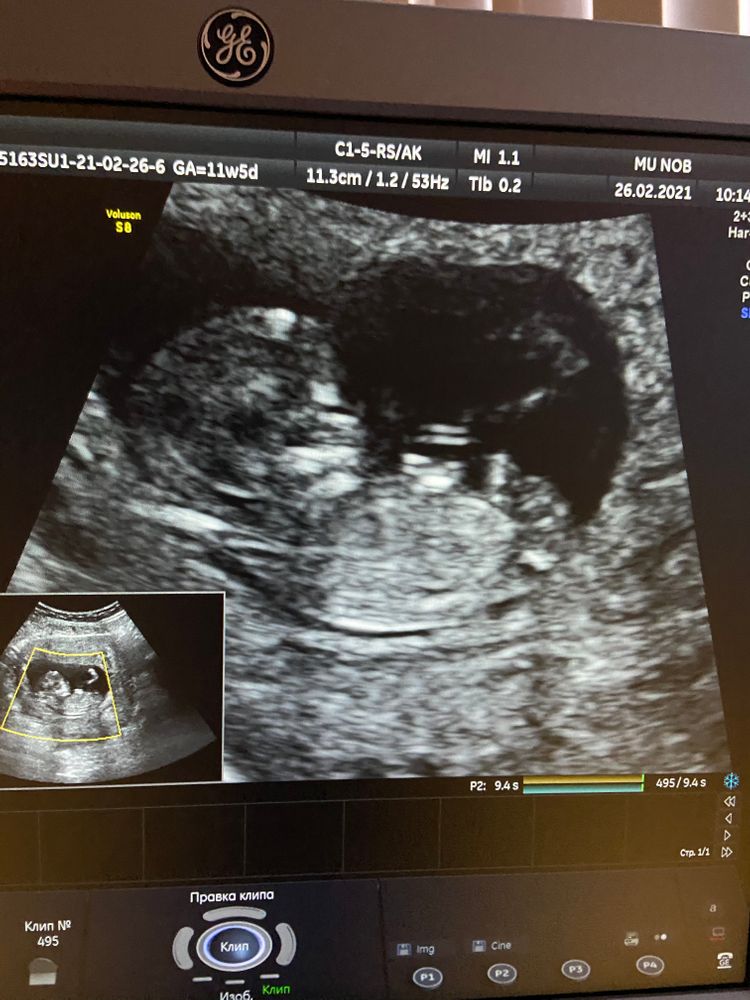

Вопросы про УЗИ, обследования и анализы: что, где, как, когда?Сегодня была на первом скрининге, срок 12 недель. Пол естественно никто не сказал под предлогом, что это скрининг а не просто узи🤦🏻♀️Но сфоткать экран дали😍

так вот любуюсь я значит своим лялечкой пузяшным, и назрел вопрос , можно ли понять кто ? Мальчик или девочка? Выделила ту часть, что вызвала вопрос😂😂😂

На фото не видно половой бугорок

Похоже на девочку. Бугорок закинут вверх. А если немного вниз опущен-мальчик. Это я на акушерку подписана,она недавно выставляла такие сравнения🙈. Но на какой неделе,не знаю точно.

Ну как по мне то что вы обвели похоже на мужские половые органы, но на этом сроке смотрят половой бугорок сбоку а не так, поэтому тут не определить )

То, что Вы обвели - не то. Это пуповина, скорее всего. Половой бугорок не видно. Ну, мне, по крайней мере))